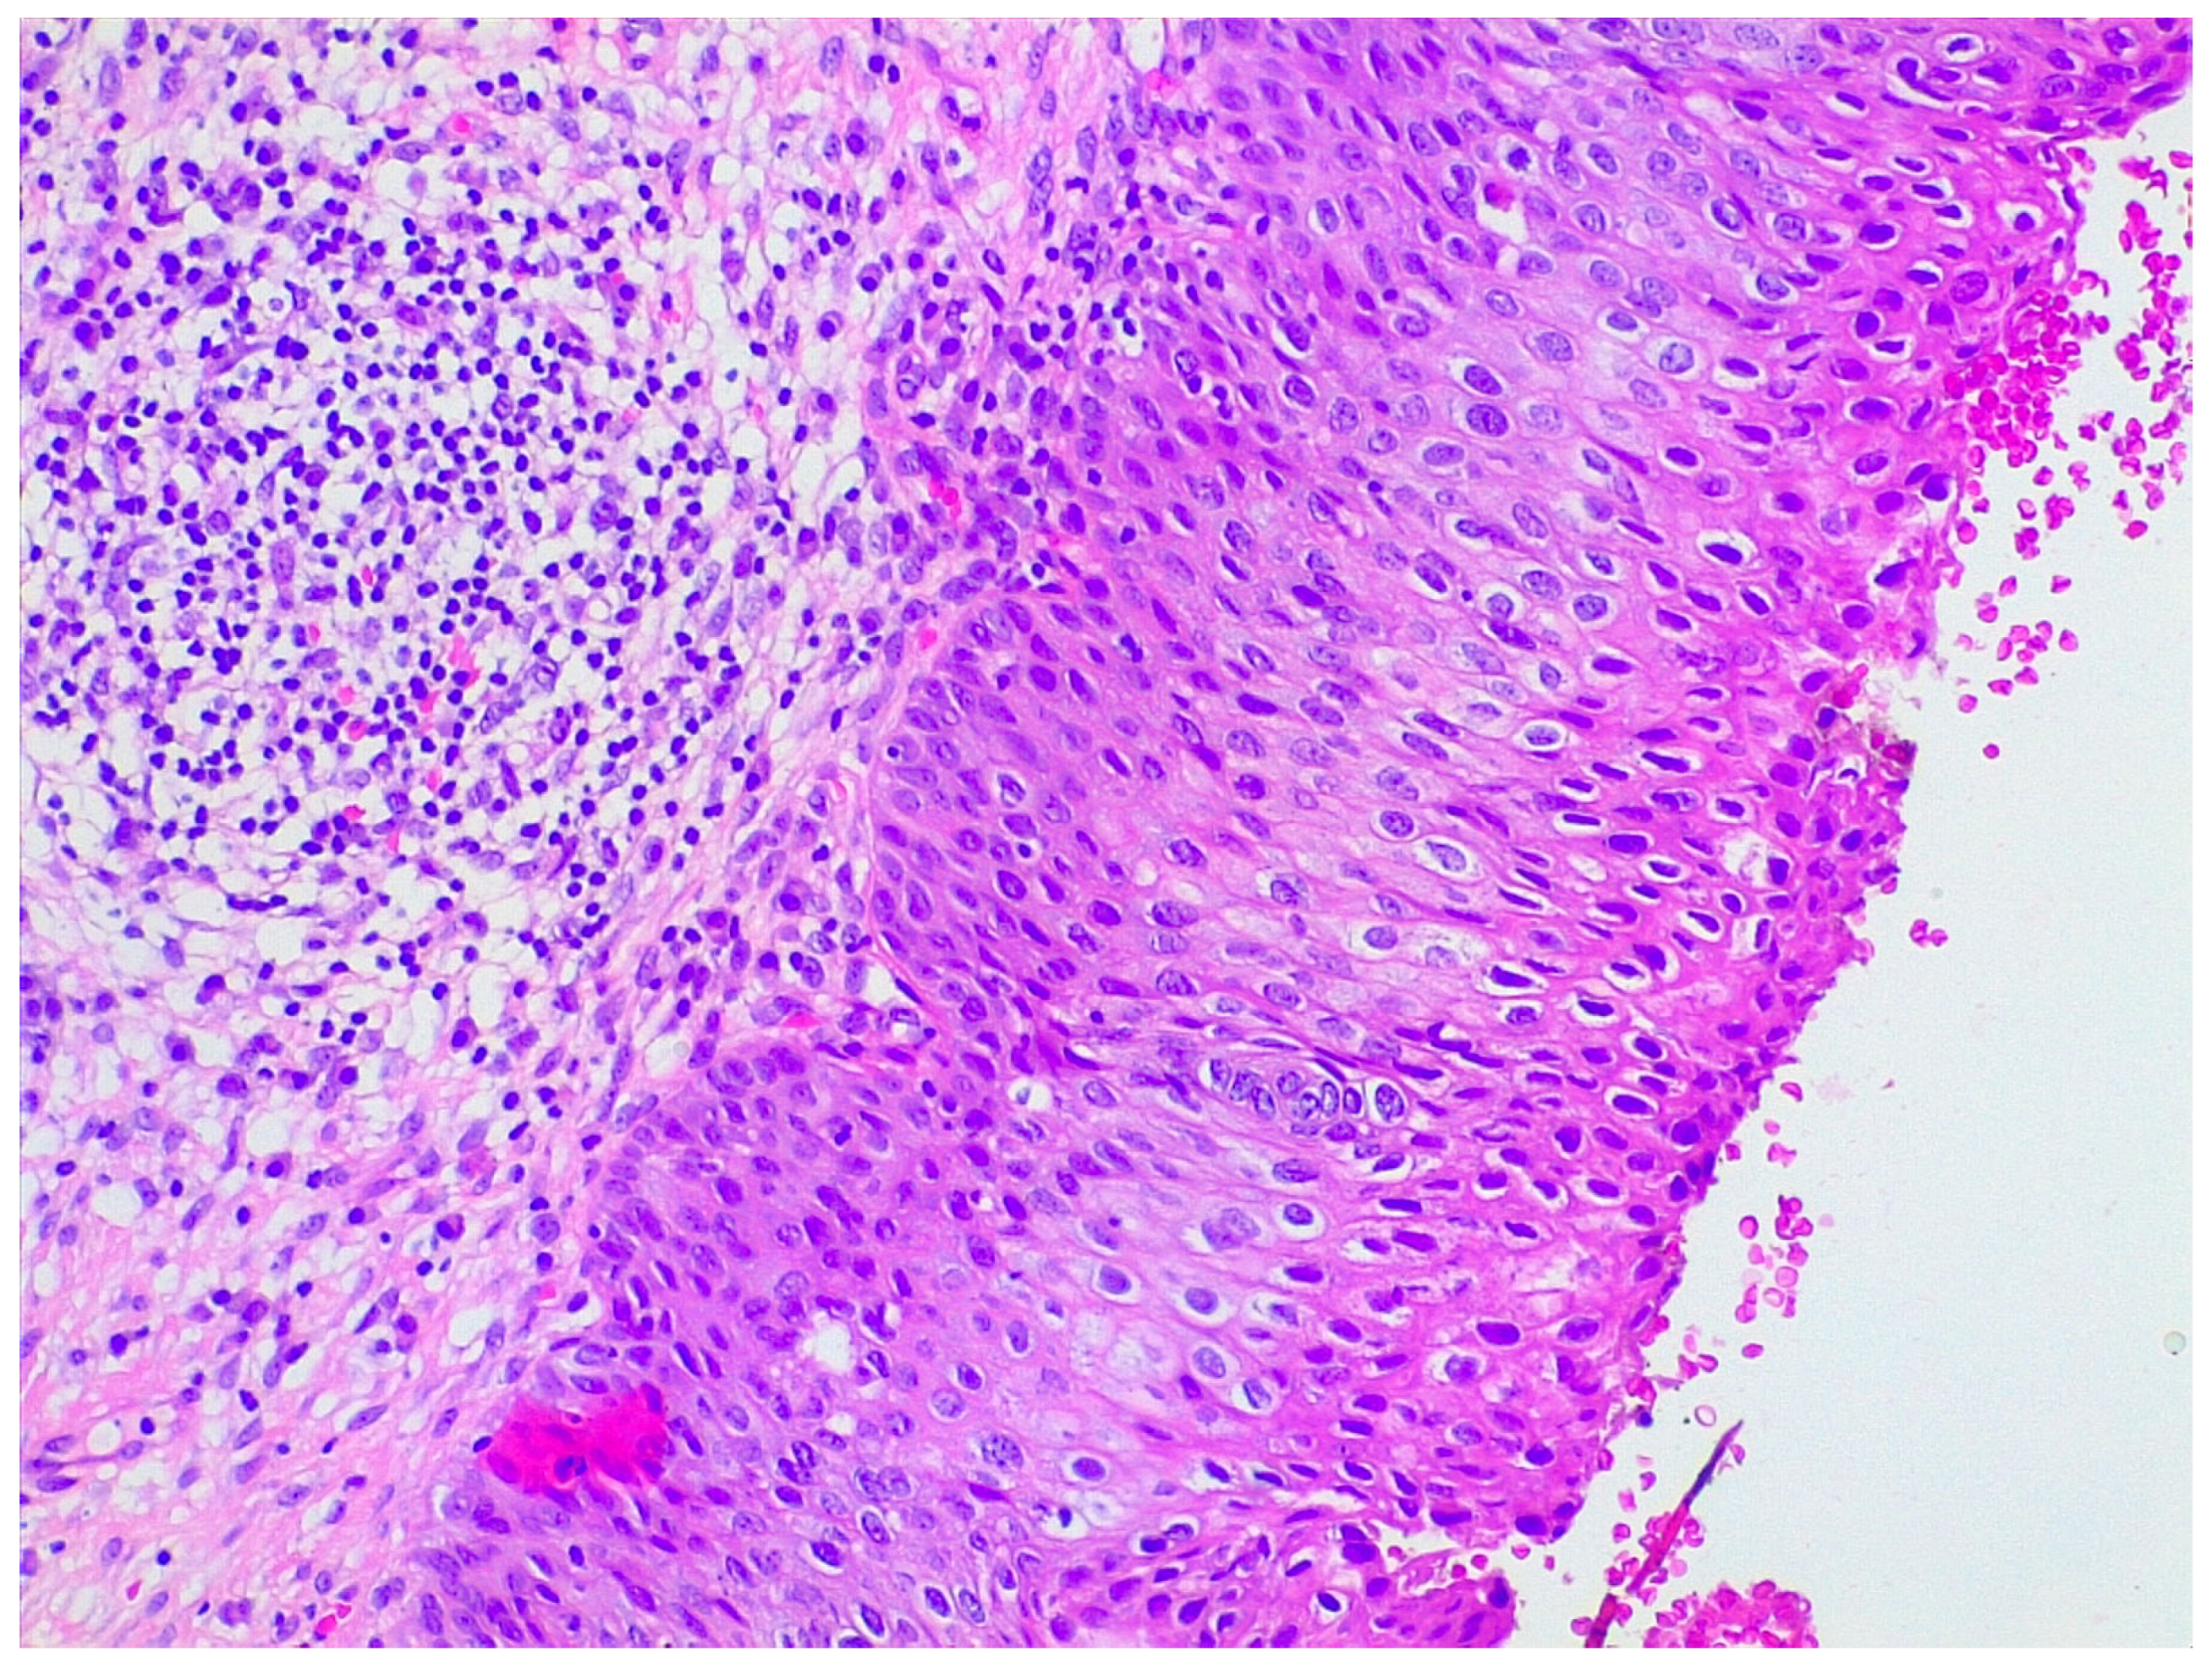

LEEP samples were sent for histological analysis already fixed in 10% formaldehyde and oriented by the gynecologist. Firstly, length, width, and wall thickness were measured for each LEEP sample; any grossly visible lesion was recorded in terms of length, width, and thickness; lesion location and its distance from margins were documented. Then, the deep margin was inked, and the full sample was submitted for histologic examination. Specimens were radially thinly sectioned (ideally 2 mm sections), ensuring each section had endocervical and ectocervical margins. They were serially submitted in a clockwise direction by putting one or two sections per cassette, depending on the size. Representative slides of the lesions were stained with hematoxylin and eosin. LEEP sections then were evaluated under the microscope by a pathologist for diagnosis and choice of the most appropriate sections for further protein expression evaluation (Figure 5).

Figure 5.

Hematoxylin and eosin staining of a patient with preneoplastic cervical disease.